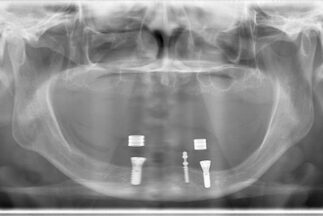

インプラント埋入後のレントゲン像

-